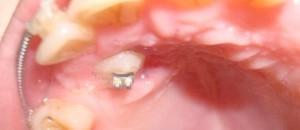

Вытяжение зуба

Этап заключается в том, что врач наклеивает брекет, крючок или замок на коронку ретинированного зуба. Данную процедуру необходимо провести в первые дни после обнажения коронки.

Далее с помощью эластических цепочек ортодонт подвязывает его к основной дуге брекет-системы и начинает поэтапное вытягивание и постановку в зубной ряд. Процесс вытяжения клыка брекетами представлен на фото.